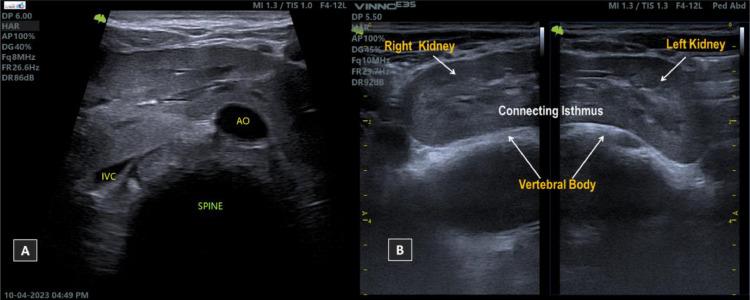

The occurrence of triple kidneys, involving a normal kidney and a malrotation horseshoe kidney, is an extremely infrequent condition. This case report demonstrates a triple, mal-rotated horseshoe kidneys coexist with an upper junction stone, alongside a normal left kidney showing normal Doppler vascularity, as observed in an ultrasound examination for 18-year-old male complaints of diffuse periumbilical pain and burning micturition. Laboratory investigation revealed normal creatinine level, and presence of urinary tract infection. Management option for this case are antibiotic therapy and surgical intervention for horseshoe kidney stone. Regular monitoring of kidney function, other radiographic imaging studies, and follow-up to assess the efficacy of the treatment, and detect any further complications are essential.

三肾(包括一个正常肾脏和一个旋转不良的马蹄肾)的情况极为罕见。本病例报告展示了一个旋转不良的马蹄形三肾与一个上极连接部结石并存,同时还有一个左肾正常,超声检查显示其多普勒血管情况正常,该病例来自一名18岁男性,主诉弥漫性脐周疼痛和排尿烧灼感。实验室检查显示肌酐水平正常,存在尿路感染。该病例的治疗方案是抗生素治疗以及针对马蹄肾结石的手术干预。定期监测肾功能、进行其他影像学检查以及随访以评估治疗效果并检测任何进一步的并发症至关重要。